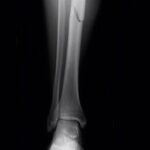

بخشی از نمونه کارها

بیماری مادرزادی اندام ها

تغییرات در ژنتیک فرد و انتقال این تغییرات از نسل به نسل میتواند منجر به بروز بیماریهای مادرزادی اندامها شود. این تغییرات میتوانند به صورت وراثتی